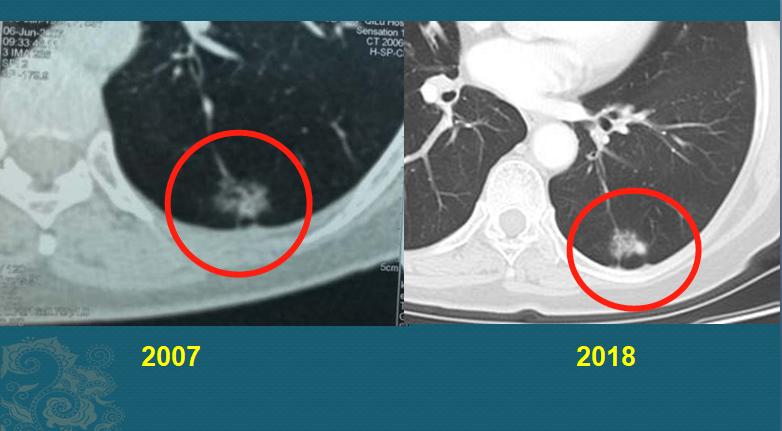

最后举一个惰性肺癌的例子,给大家定定神

这是一位中年女性,在2007年胸部CT体检,发现左下肺混合磨玻璃结节,边界不清,伴有胸膜牵拉:

她每年谨慎复查CT,结节一直没什么变化,直到11年后才开始有密度增加,做了手术切除,病理是浸润性肺腺癌。

今天的几个病例都比较极端,慢癌不要紧,快癌只要定期体检(推荐每年一次,尤其是老年人),也能阻止它发展。